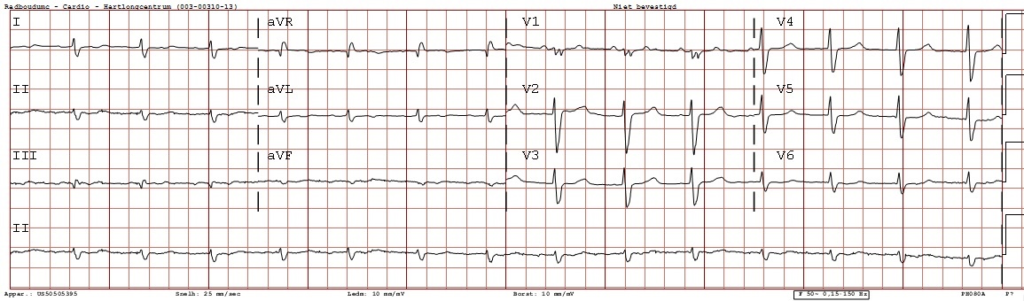

Een 75-jarige man met onbegrepen hartfalen. Wat ziet u op het elektrocardiogram?

Figuur 1: ECG

Een boezemritme met een kamerrespons 75-90/min. De hartas is naar links gedraaid. De QRS-duur is 114 ms (intraventriculaire geleidingsvertraging) en QTc 480 ms. Er zijn opvallend extreem lage voltages in de extremiteitsafleiding. Het is opmerkelijk dat de criteria voor linkerkamerhypertrofie negatief zijn, ondanks de sterk hypertrofische ventrikel op de MRI.